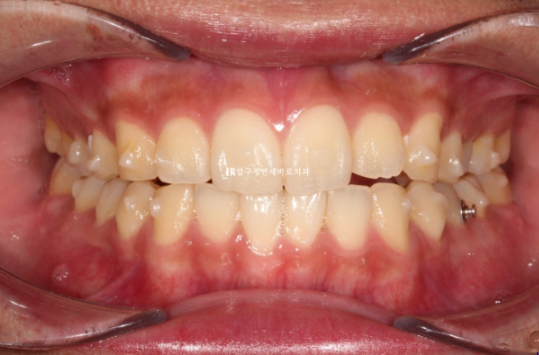

24.10

걱정하시는 교합도 좋습니다.

인비절라인은 교합이 안 좋게 끝난다 라는 편견을 깨기 위해 노력합니다.

배열도 좋습니다.